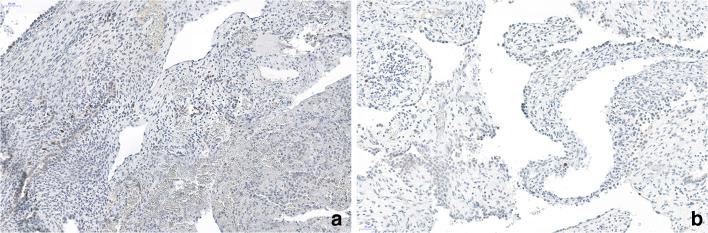

Congenital pulmonary airway malformation (CPAM) occurs most commonly in infants. It is divided into 5 types. The most common types 1 and 2 are cystic, type 0 presents as bronchial buds without alveolar tissue, most likely corresponding to alveolar dysgenesis, while type 3 is composed of branching bronchioles and appears as a solid lesion. A defect in the epithelial-mesenchymal crosstalk might be the underlying mechanism for all. Type 4 is a peripheral cystic lesion with a thin cyst wall covered by pneumocytes. CPAM 4 has been mixed up with pleuropulmonary blastoma (PPB) type I and some authors question its existence. We investigated five cases of CPAM type 4 for the presence or absence of rhabdomyoblasts, and for markers associated with CPAM development. In addition, all cases were evaluated for mutations within the Dicer gene and for mutations of the RAS family of oncogenes. All five cases showed smooth muscle actin and desmin-positive cells; however, only one case showed a few cells positive for MyoD. The same case showed a mutation of Dicer 1. All cases were negative for mutations of the RAS family of genes. Fibroblast growth factor 10 was similarly expressed in all cases, and thus cannot be used to differentiate CPAM4 from PPB-I. Low expression of the proliferation marker Ki67 was seen in our CPAM 4 cases and the probable PPB-I case. YingYang-1 protein seems to play an active role in the development of PPB-I. CPAM 4 can be separated from PPB-I based on the presence of rhabdomyoblasts and mutations in Dicer 1 gene. These cells might not be numerous; therefore, all available tissue has to be evaluated. As CPAM 4 morphologically looks very similar to PPB-I, it might be speculated, that there exists a potential for progression from CPAM 4 to PPB-I, by acquiring somatic mutations in Dicer 1.

先天性肺气道畸形(CPAM)最常发生于婴儿。它可分为 5 型。最常见的 1 型和 2 型为囊肿型,0 型表现为无肺泡组织的支气管芽,最可能对应肺泡发育不全,而 3 型由分支细支气管组成,表现为实性病变。上皮-间充质细胞相互作用的缺陷可能是所有这些的潜在机制。4 型为薄壁含气囊肿,由肺泡细胞覆盖。CPAM 4 曾与肺胚细胞瘤(PPB)I 型相混淆,一些作者质疑其存在。我们研究了 5 例 CPAM 4 型,观察有无横纹肌母细胞及与 CPAM 发生相关的标志物。此外,所有病例均评估 Dicer 基因突变及 RAS 家族癌基因突变情况。所有 5 例均显示平滑肌肌动蛋白和结蛋白阳性细胞,但仅有 1 例可见少量肌源性分化蛋白(MyoD)阳性细胞。同 1 例存在 Dicer1 基因突变。所有病例均未见 RAS 家族基因突变。所有病例的成纤维细胞生长因子 10 表达相似,因此不能用于区分 CPAM4 与 PPB-I。Ki67 增殖标志物在我们的 CPAM 4 病例和可能的 PPB-I 病例中低表达。YingYang-1 蛋白似乎在 PPB-I 的发生中发挥积极作用。CPAM 4 可根据横纹肌母细胞的存在及 Dicer 1 基因突变与 PPB-I 区分。这些细胞可能数量不多,因此需要评估所有可用组织。由于 CPAM 4 在形态上与 PPB-I 非常相似,可以推测,通过获得 Dicer 1 体细胞突变,CPAM 4 可能有向 PPB-I 进展的潜能。